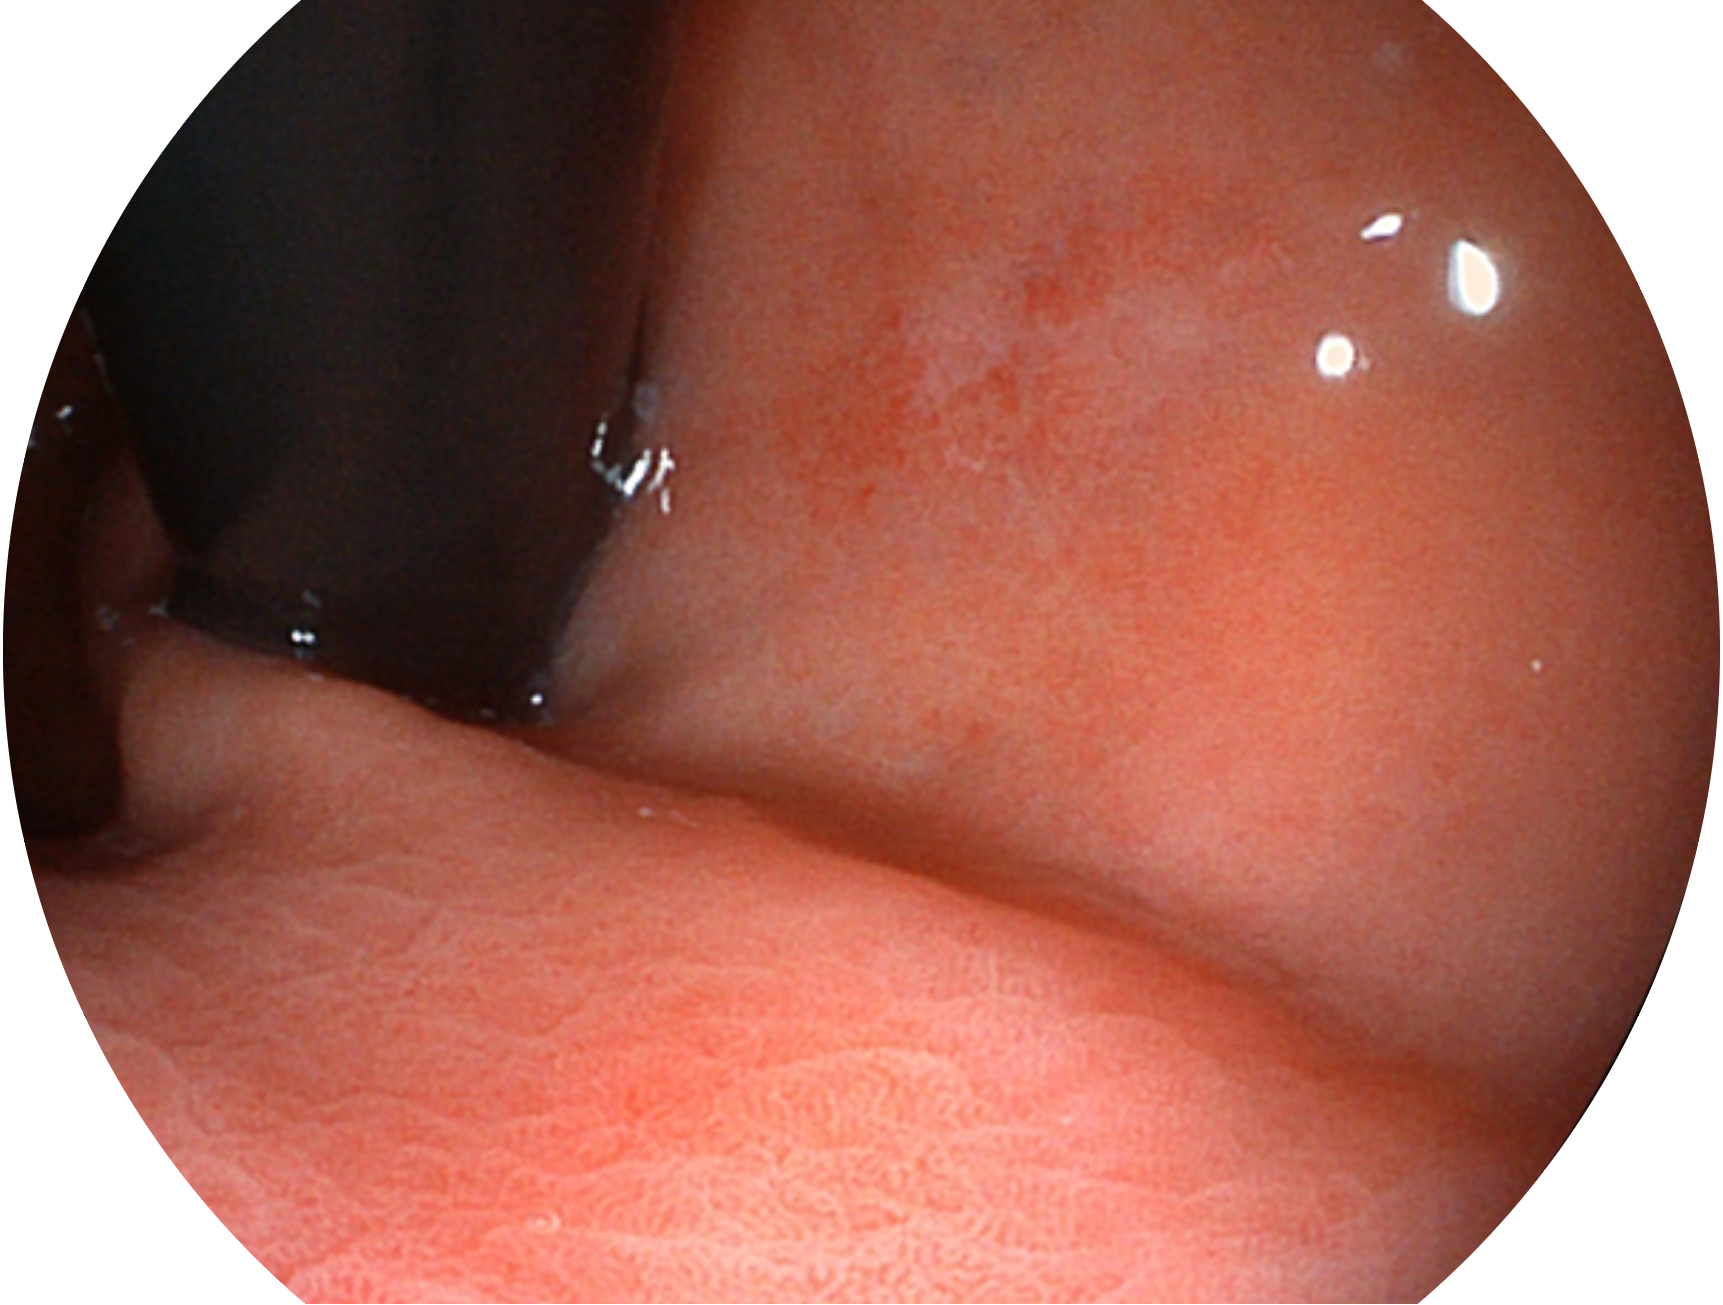

亚星官网新开发的内镜染色技术,主要是基于多波长LED 光源的开发,VLS-55Q 四波长LED 光源是由四个不同颜色的LED光按照相应照明模式所规定的特定发光比例进行合束后形成,合束后形成的照明光的光谱由红光、绿光、蓝光及蓝紫光这四个不同的波段范围构成。具有更高光谱自由度,通过光谱比例的控制,实现了聚谱成像技术,英文全称为“Spectral Focused Imaging, SFI”,缩写为“SFI”和光电复合染色成像技术,英文全称为“Versatile Intelligent Staining Technology, VIST”,缩写为“VIST”。